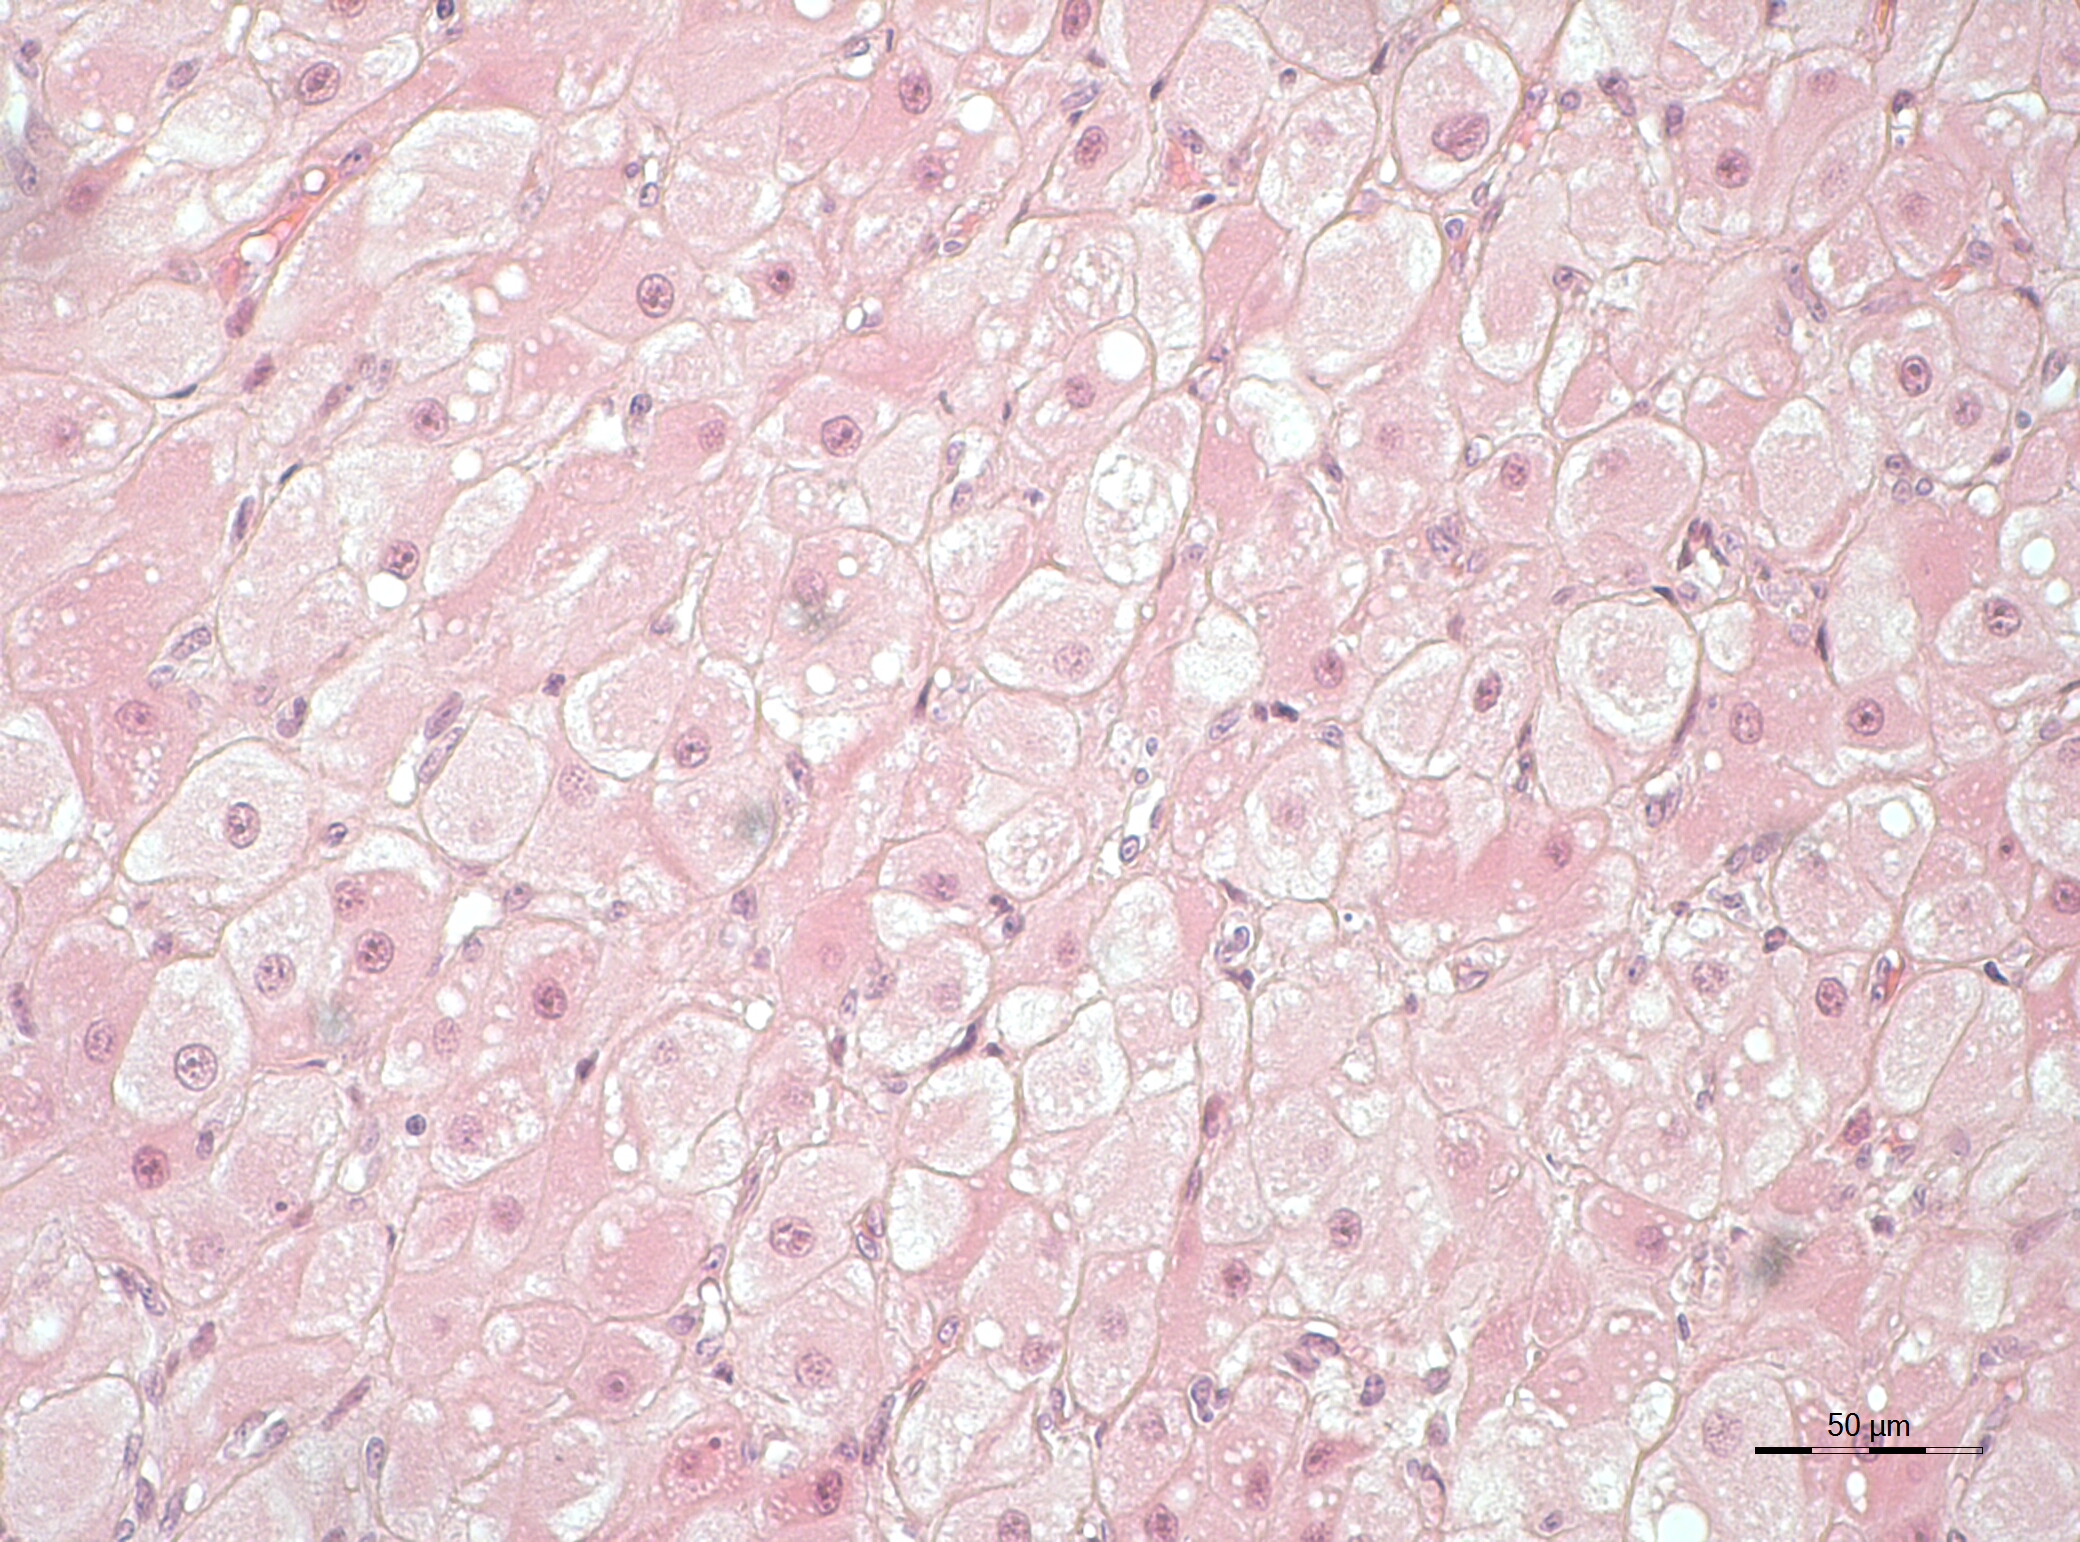

„Es ist uns gelungen, aus Gelbkörper-Proben von Hauskatzen Zellen zu isolieren und zu kultivieren, die auch funktionell aktiv waren, also Progesteron produzierten. So konnten wir die regulatorische Wirkung verschiedener Effektoren auf diese Zellen testen“, sagt Beate Braun, Leiterin der Leibniz-IZW Untersuchung. Die Methodik der Zellkultur erlaubt es, Untersuchungen durchzuführen, ohne Versuche an Hauskatzen oder Wildtieren vorzunehmen. Getestet wurden die Wirkungen eines potenziell gelbkörpererhaltenden Hormons (LH – luteinizing hormone) und eines potenziell gelbkörperabbauenden Hormons (PGF2α – Prostaglandin F2α). Das Team konnte zeigen, dass – abhängig vom Entwicklungsstadium des Gelbkörpers – die Zellen auf die Anwesenheit dieser Hormone reagierten und dadurch mehr oder weniger Progesteron produzierten.

„Das Besondere an der Untersuchung ist, dass wir die eigens für Hauskatzen entwickelte Methode auch auf unser rares Probenmaterial von wildlebenden Katzenarten wie dem Afrikanischen und Asiatischen Löwen, der Asiatischen Goldkatze und dem Java-Leopard erfolgreich anwenden konnten. Das zeigt uns, dass es möglich ist, verwandte Tierarten für den Erkenntnisgewinn zu nutzen, und die Techniken als auch das Wissen auf bedrohte Arten zu übertragen“, erklärt Michał Hryciuk, der mit diesen erfolgreichen Untersuchungen seine Promotion im Fach Reproduktionsbiologie abschließen wird. Ziel ist es nun, auch Gelbkörperzellen von Luchsen ins Visier zu nehmen, um deren Besonderheiten bezüglich der Langlebigkeit von Gelbkörpern zu untersuchen.